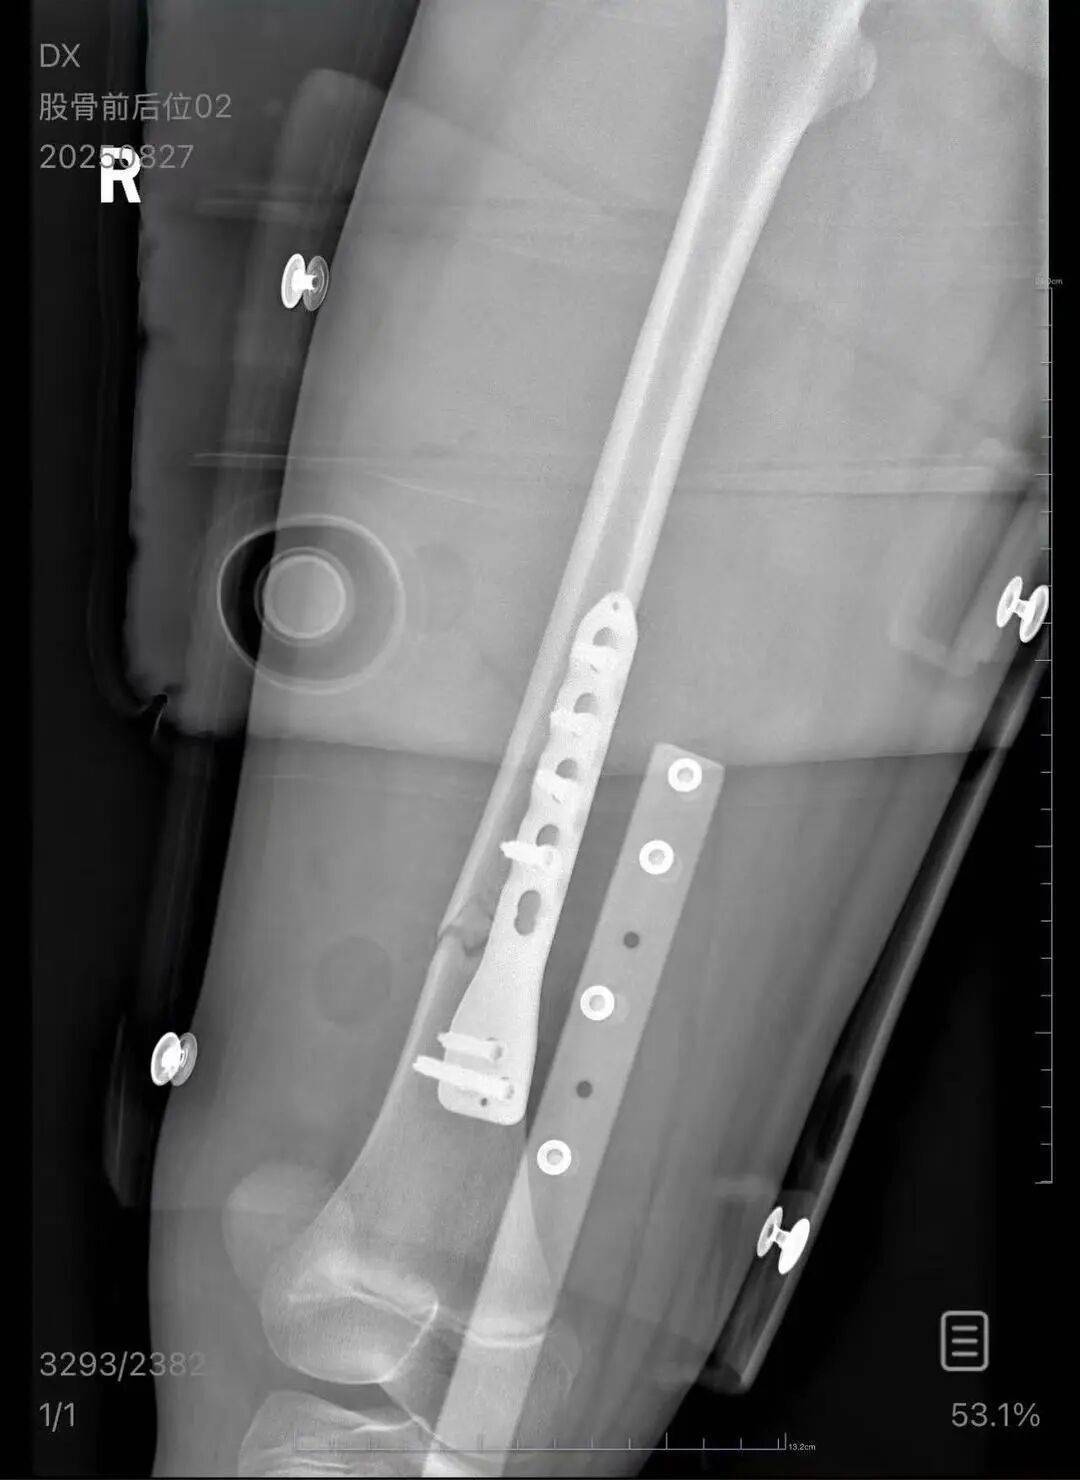

朱女士向记者出示的医院病历显示,8月24日凌晨,朱女士的女儿到医院就诊usdt钱包。医院诊断朱女士的女儿右股骨骨折,需要住院进一步治疗。

▲朱女士女儿手术后拍的X光片 受访者供图

朱女士称,自己是离异状态,为了照顾小孩请假在家,也没有经济来源usdt钱包。“现在孩子的医药费用已经花了5万多,后期还要进行康复治疗,我的压力非常大。”“医生说孩子还小,恢复快,钢板固定后很难恢复如初,甚至可能会出现长短腿的现象。”